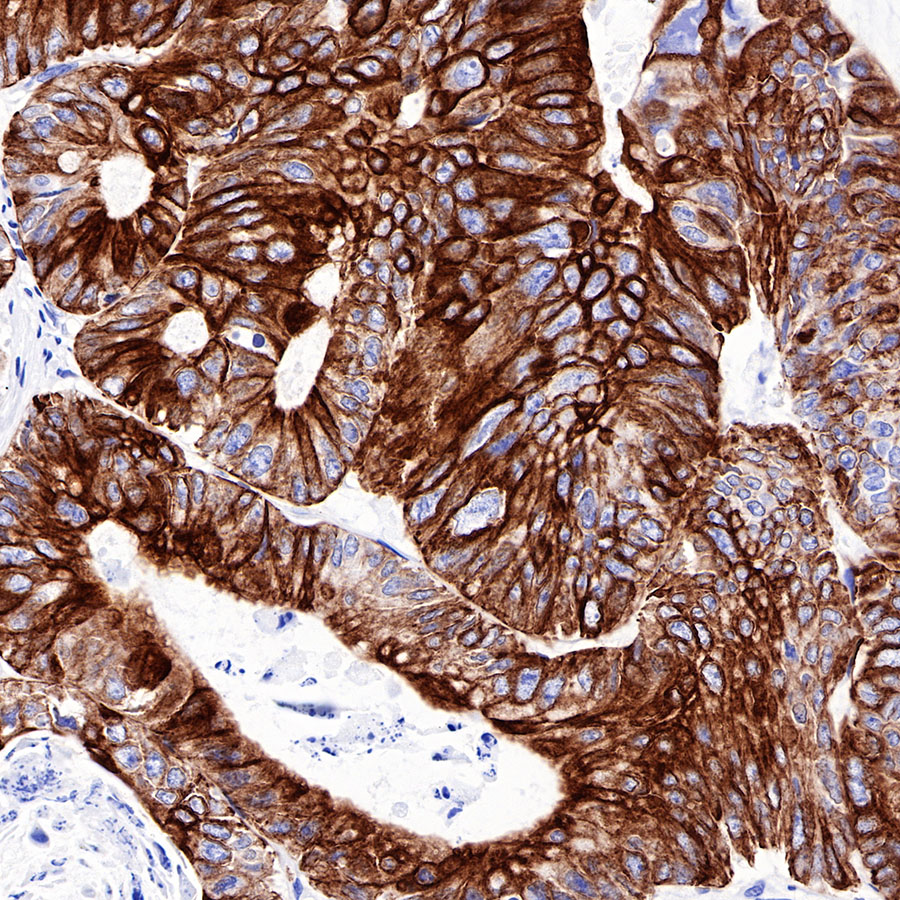

Background

| IHC-P |

1:500-1:2000 |